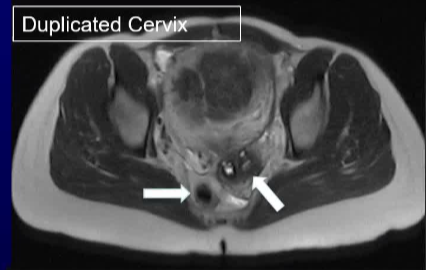

47 岁的 G1P1 女性因持续两年的月经过多症状前来就诊。 症状还包括盆腔痉挛性疼痛、尿频和背痛。妇科病史显示存在一种已知的苗勒管异常(MDA)。按照方案要求进行了盆腔磁共振成像(MR)检查,以评估子宫肌瘤栓塞术(UFE)的情况。检查结果显示为单角子宫,其主导的右侧子宫角存在强化的全层和黏膜下肌瘤,左侧则有一个相通的原始子宫角。 MR 还显示右侧有一个孤立的肾脏,右侧子宫动脉占主导地位,而左侧的子宫动脉和卵巢动脉均无法辨认。 子宫肌瘤被认为是导致月经过多和下腹肿块症状的原因。